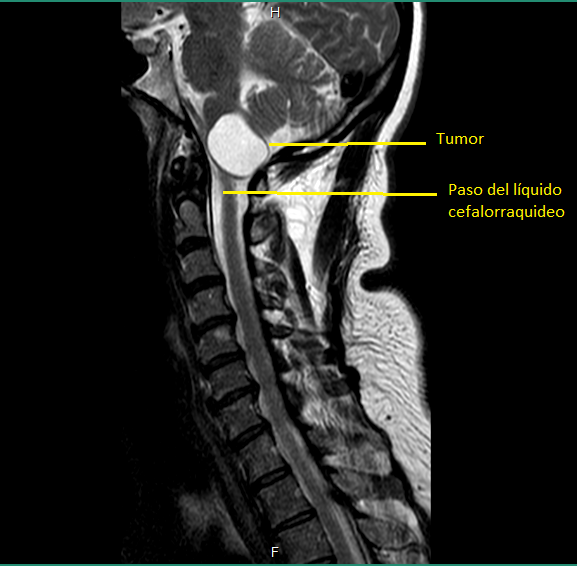

Dos días después, por recomendación y presión, conseguí una cita urgente con un neurocirujano del mismo hospital. Un hombre de mediana edad, de semblante relajado y afable pero de pocas palabras, me recibió y me preguntó cortante por qué había acudido con él. Le conté del ortopedista y le mostré los estudios. Lo confirmo y agregó: "Por la posición donde está alojado el tumor, junto al cerebelo, muy cerca del cuarto ventrículo, es peligroso ya que es de gran tamaño y está bloqueando el paso de líquido cefalorraquídeo a la columna". Obvio no entendí nada de lo que dijo en ese momento, sus palabras no tenían ningún significado para mí, pero por la expresión de su rostro entendí que era algo serio.

El 13 de agosto de 2019, ya con la resonancia de cráneo y los papeles del seguro, acudí con el doctor. Después de verlos me confirmó: "Es un tumor (quiste) benigno con el que nació. Se desconoce por qué se forman, pero una teoría es que son residuos de placenta que se quedan cuando se forma el producto en el vientre. Eso no es un tema, mi principal preocupación es su ubicación y tamaño mide: 3.3cm x 2.1cm x 1.7cm y se comunica con el cuarto ventrículo, y está obstruyendo el paso de líquido cefalorraquídeo a la columna". Me advirtió: "Va a ser un procedimiento muy doloroso, así que debes de estar consciente de ello". Llenó los papeles del seguro con carácter de urgente, con el diagnóstico: Tumor de comportamiento incierto o desconocido en el encéfalo y del sistema nervioso central.